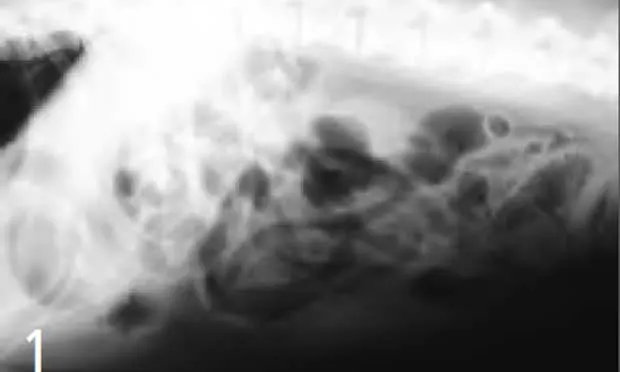

Exploratory laparotomy was done, and a whole compressed vegetable chew treat was removed from the stomach by gastrotomy (Figure 3) and pieces of chew treats were removed from the jejunum by two enterotomy incisions (Figure 4).

Figure 3. At the time of surgery, a whole compressed vegetable chew treat was removed from the patient’s stomach.